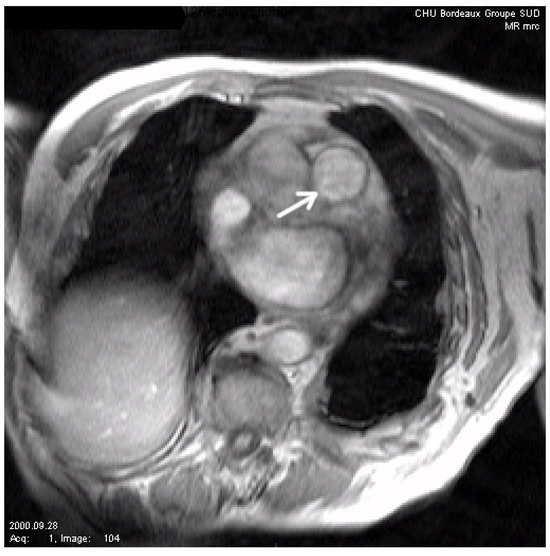

4.2. Image Segmentation

- and : it corresponds to our proposed segmentation model under geometric conditions.

- and : it corresponds to a basic segmentation model without geometric conditions.